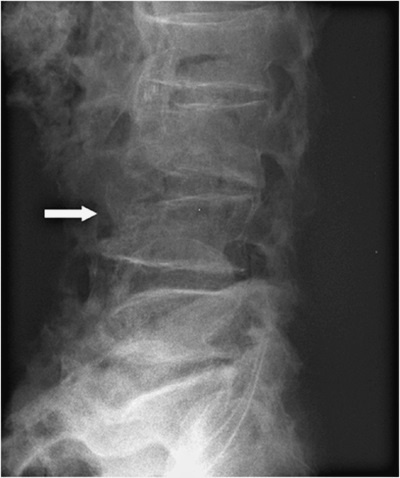

На 3-й день после состоявшегося осмотра участковым врачом выполнена рентгенограмма поясничного отдела позвоночника (см. рис. 1).

Заключение в поликлинике: остеохондроз поясничного отдела позвоночника, остеофиты всех поясничных позвонков. Компрессионные изменения L4.

Рисунок 1. Рентгенограмма поясничного отдела позвоночника